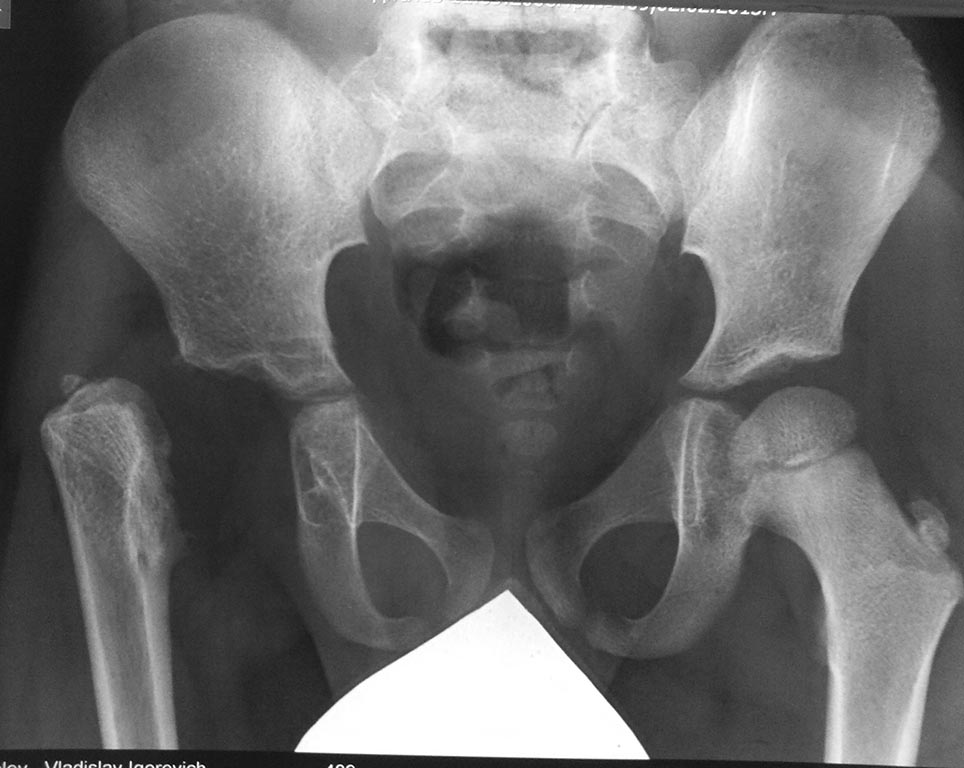

Ребенок, гражданин Украины, на 1 недели после беременности, со слов родителей, перенес "остеомиелит" (я так понимаю был гнойный коксит)

1 год |  5 лет | Курс лечения антибиотиками, никакой иммобилизации, выписка - вообщем без особенностейНа этапных профосмотрах заподозрена дисплазия правого тазобедренного сустава, лечение в стременах (консультации специалистов "Охматдета" - Украинский центр республиканского масштаба), потом отводящей шиной, этапные УЗИ с заключениями о формировании дисплазии и т.д. Первый рентген-контроль сделан в 1 год (прикладывается)На данный момент ребенку 5 лет, ходит, немного "нахрамывая" после длительных нагрузок, на серьезный дискомфорт и болевой синдром особенно не жалуетсяПоследний снимок свежий, сделан в 5 лет

Вопросов у родителей несколько: 1)Нужно ли делать оперативное вмешательство сейчас или ждать какое то время 2)Если делать оперативное вмешательство, то какое будет оптимальным 3)Каковы риски инфекционных осложнений при различных оперативных вмешательствах (по описанию родителей рекомендовано 1.остеотомия с накостным остеосинтезом для мобилизации вертела вместо головки во впадину - предлагается в "Охматдете" 2.лечение с помощью аппарата Илизарова рекомендовано при заочной консультации по рентген-снимку со специалистами одной из больниц С-Петербурга (родители не указывают, какой именно))

Учитывая вполне удовлетворительную функцию конечности в данный момент, вряд ли предлагаемые оперативные вмешательства улучшат положение. А вот осложнить дальнейшее возможное эндопротезирование вполне могут.

Не нужно лечить рентгенограмму.